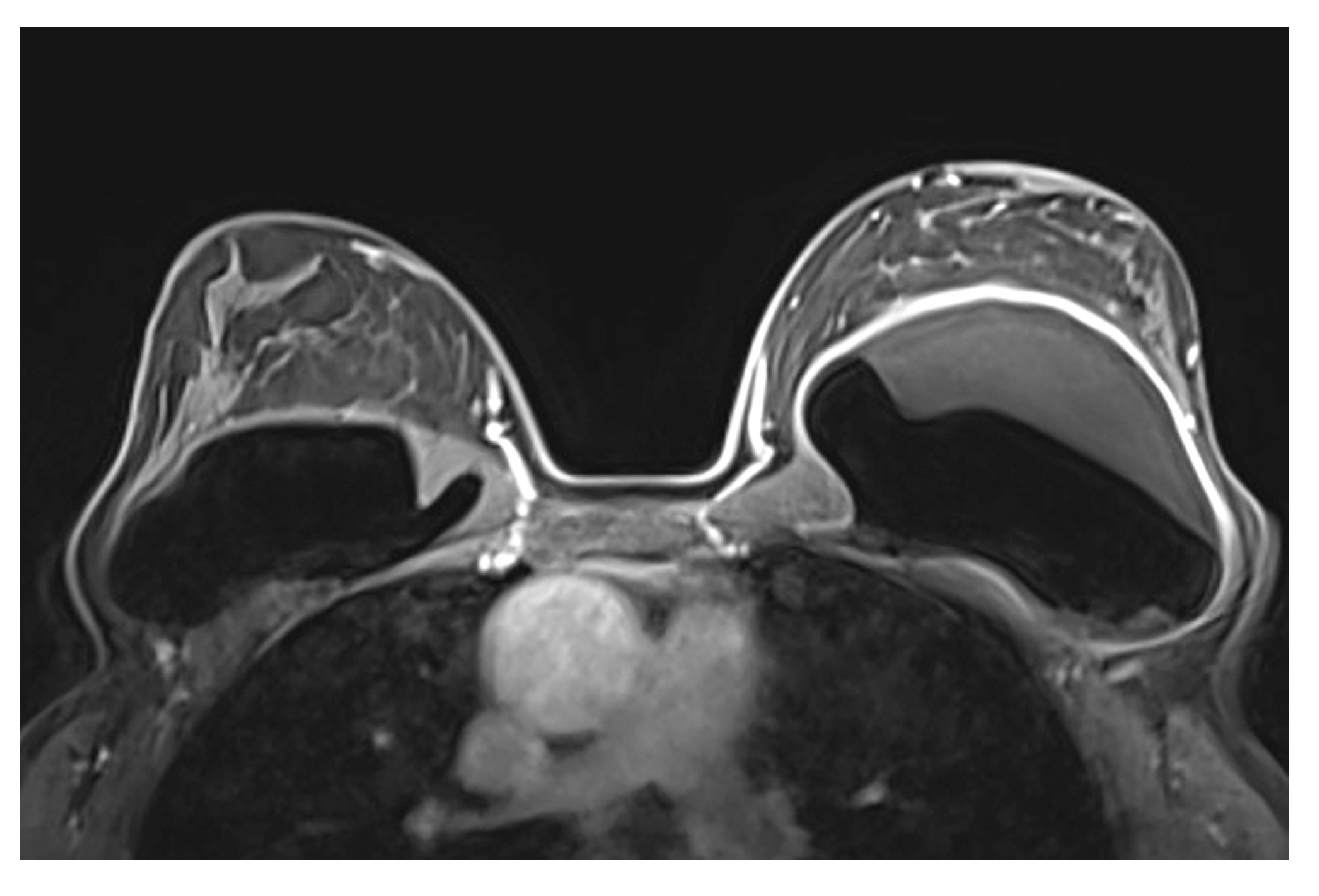

5.2.6. Breast Implant Associated Atypical Large Cell Lymphoma (BIA-ALCL)

- Sharma, B.; Jurgensen-Rauch, A.; Pace, E.; Attygalle, A.D.; Sharma, R.; Bommier, C.; Wotherspoon, A.C.; Sharma, S.; Iyengar, S.; El-Sharkawi, D. Breast Implant-associated Anaplastic Large Cell Lymphoma: Review and Multiparametric Imaging Paradigms. Radiographics 2020, 40, 609–628. [Google Scholar] [CrossRef] [PubMed]

- Adrada, B.E.; Miranda, R.N.; Rauch, G.M.; Arribas, E.; Kanagal-Shamanna, R.; Clemens, M.W.; Fanale, M.; Haideri, N.; Mustafa, E.; Larrinaga, J.; et al. Breast implant-associated anaplastic large cell lymphoma: Sensitivity, specificity, and findings of imaging studies in 44 patients. Breast Cancer Res. Treat. 2014, 147, 1–14. [Google Scholar] [CrossRef] [PubMed]

- Rotili, A.; Ferrari, F.; Nicosia, L.; Pesapane, F.; Tabanelli, V.; Fiori, S.; Vanazzi, A.; Meneghetti, L.; Abbate, F.; Latronico, A.; et al. MRI features of breast implant-associated anaplastic large cell lymphoma. Br. J. Radiol. 2021, 94, 20210093. [Google Scholar] [CrossRef]